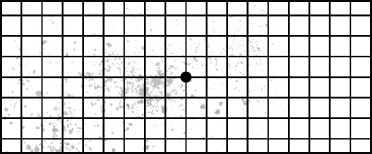

망막박리가 있는 경우

정상안